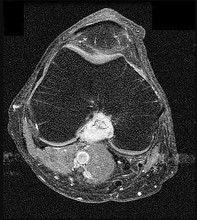

Question 9:

A 15-year-old male presents with deep knee pain. Radiographs reveal a mixed lytic and sclerotic lesion in the distal femur metaphysis with a "sunburst" periosteal reaction. Biopsy confirms high-grade conventional osteosarcoma. What is the most appropriate next step in management?

Correct Answer: Neoadjuvant chemotherapy followed by wide surgical resection and adjuvant chemotherapy

Explanation:

The standard of care for high-grade conventional osteosarcoma is neoadjuvant (preoperative) chemotherapy, followed by wide surgical resection (limb-sparing surgery if feasible), and then adjuvant (postoperative) chemotherapy.